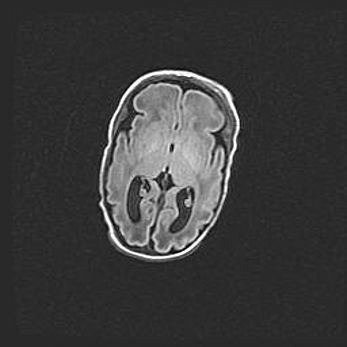

Церебральная ишемия II.

Возраст: 5 дней

Вес: 3400 г

Пол: женский

Окружность головы: 35 см

Срок гестации: 39 недель

Церебральная ишемия – это заболевание, характеризующееся недостаточностью (гипоксией) либо полным прекращением (аноксией) снабжения мозга кислородом по причине закупорки одного или нескольких сосудов. Это приводит к  что метаболическим расстройствам различной степени тяжести в тканях головного мозга, развитию коагуляционных некрозов и гибели нейронов.